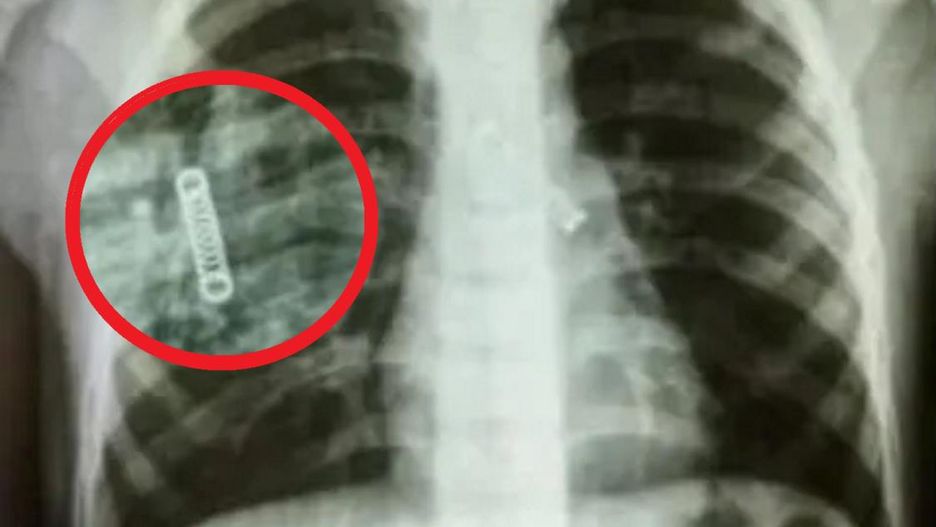

Pięcioletni chłopiec od grudnia 2022 roku zmagal się z silnym kaszlem, a jego zaniepokojeni rodzice nie byli w stanie odnaleźć źródła problemu. Po przeprowadzeniu badań, ujawniło się niespodziewane wyjaśnienie. Wynikało z nich, że w lewym płucu 5-latka lekarze odkryli niewielki metalowy obiekt.

Gdy dokonano badania rentgenowskiego płuc, okazało się, że chłopiec miał w jednym z nich małą metalową sprężynę, tkwiła tam od 3 miesięcy, nie ustalono jednak, jak się tam znalazła.

Wczesnym rankiem 8 marca zespół specjalistów pod przewodnictwem doktora Carlosa Morinigo, z sukcesem wydobył ciało obce z płuca dziecka. Lekarz prowadzący działania, opisał interwencję jako bardzo skomplikowaną - sprężyna, która znajdowała się w płucu, zdążyła już spowodować liczne szkody.